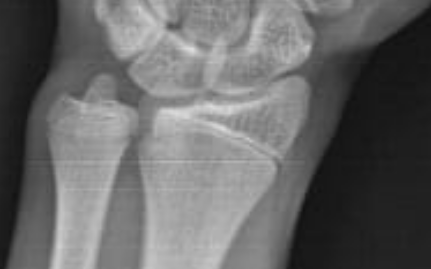

röntgenin hiç iç açıcı değil sadece bunu söyleyeceğim